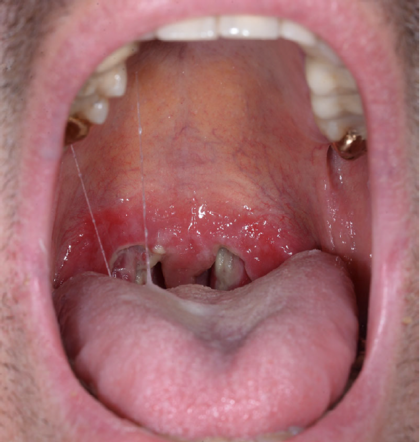

Angina specifica, auch Angina syphilitica, beschreibt die Syphilis der Tonsillen und ist eine eher seltene Manifestation der sekundären Syphilis (1). Wie im beschriebenen Fall präsentiert sie sich in der Regel als bilaterale Tonsillitis begleitet von einer diffusen Pharyngitis (2). Differenzialdiagnosen umfassen alle virale und bakteriell verursachte Halsentzündungen wie Streptokokken-Angina, Diphtherie oder Epstein-Barr-Virus-assoziierte Tonsillitis sowie die Angina agranulocytotica (3). Syphilis, verursacht durch die Spirochäte Treponema pallidum subspecies pallidum (4 ), ist eine sexuell übertragbare Infektion. Weltweit ist die Inzidenz in den vergangenen 30 Jahren gestiegen, mit einem besonders alarmierenden Anstieg seit 2010 in einkommensstarken Regionen wie den Vereinigten Staaten und Europa (5–7).

In Deutschland wurden im Jahr 2022 insgesamt 8305 Fälle registriert, was einer Inzidenz von zehn Fällen pro 100 000 Einwohner entspricht (8). Die höchsten Syphilis-Inzidenzen in Deutschland wurden aus den Metropolregionen Berlin, Köln und München gemeldet; am häufigsten betroffen waren Männer im Alter von 30–39 Jahren. Sexuelle Kontakte zwischen Männern waren bei weitem der häufigste vermutete Übertragungsweg (85,6 %) (8). Syphilis tritt in drei unterschiedlichen Stadien auf und wird aufgrund ihrer vielfältigen klinischen Erscheinungsformen auch als „der große Imitator“ bezeichnet. Die primäre Syphilis erscheint typischerweise 2 bis 6 Wochen nach der Infektion als schmerzloses induriertes Ulkus an der Stelle, die mit der aktiven Läsion des Sexualpartners in Kontakt gekommen ist. Sie findet sich am häufigsten im Genitalbereich, gefolgt vom Mundbereich. Hier können alle Strukturen wie Lippe, Zunge, Mundschleimhaut, Tonsillen und Zahnfleisch betroffen sein (9). Die sekundäre Syphilis entwickelt sich gleichzeitig oder bis zu circa 6 Monate nach Abheilung des Primärstadiums und ist oft durch einen nichtjuckenden Ausschlag mit Beteiligung von Handflächen und Fußsohlen gekennzeichnet (10). Darüber hinaus können systemische Symptome wie Fieber, generalisierte Lymphadenopathie, Alopezie sowie – bei einem kleinen Teil der Patienten – Condylomata lata beobachtet werden (4). Bei bis zu 22 % der Fälle sekundärer Syphilis kommt es zu einer oralen Beteiligung, die sich meist in Form von Schleimhaut-Maculae oder -Ulzerationen manifestiert (11). Die Syphilis im tertiären Stadium ist nicht mehr ansteckend und manifestiert sich bei etwa 15 % der unbehandelten Fälle in Form von Gummen – proliferativen, granulomatösen, teils destruktiven Läsionen –, die auch in der Mundhöhle auftreten können. Dort finden sie sich häufig entlang der Mittellinie von Gaumen und Zunge und können ulzerieren (9).